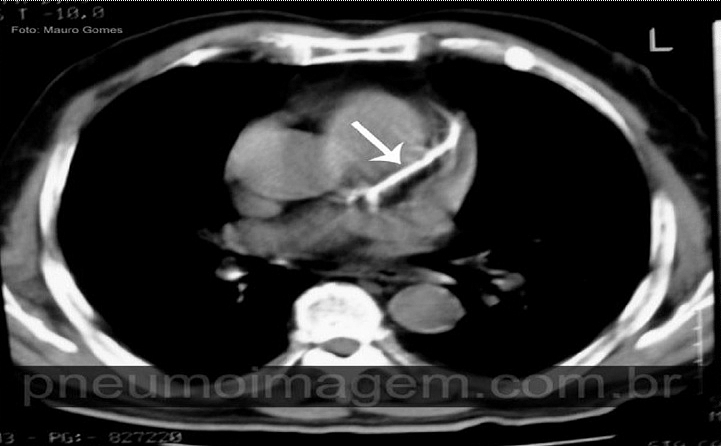

Veja imagens de calcificação coronariana no PneumoImagem, clicando aqui.